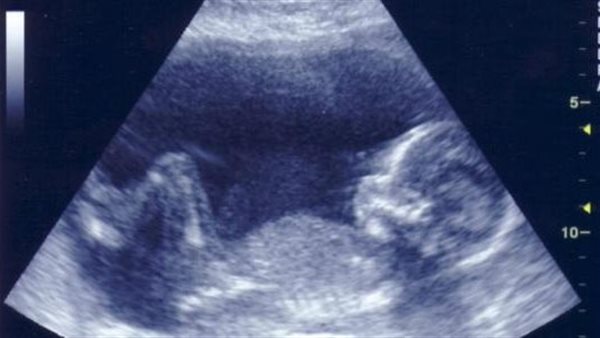

التلقيح الاصطناعي ونوع الجنين

وبحسب خبراء الصحة، يعمل التلقيح الاصطناعي على تقريب العائلات من أحلامها، خطوة بخطوة، ولكن أشارت عدد من الدراسات إلى أن هناك بعض الأساليب التي تتضمن تحليل الأجنة التي تم إنشاؤها من خلال التلقيح الاصطناعي لتحديد خصائص وراثية محددة، والتي يمكن أن تشمل الجنس.